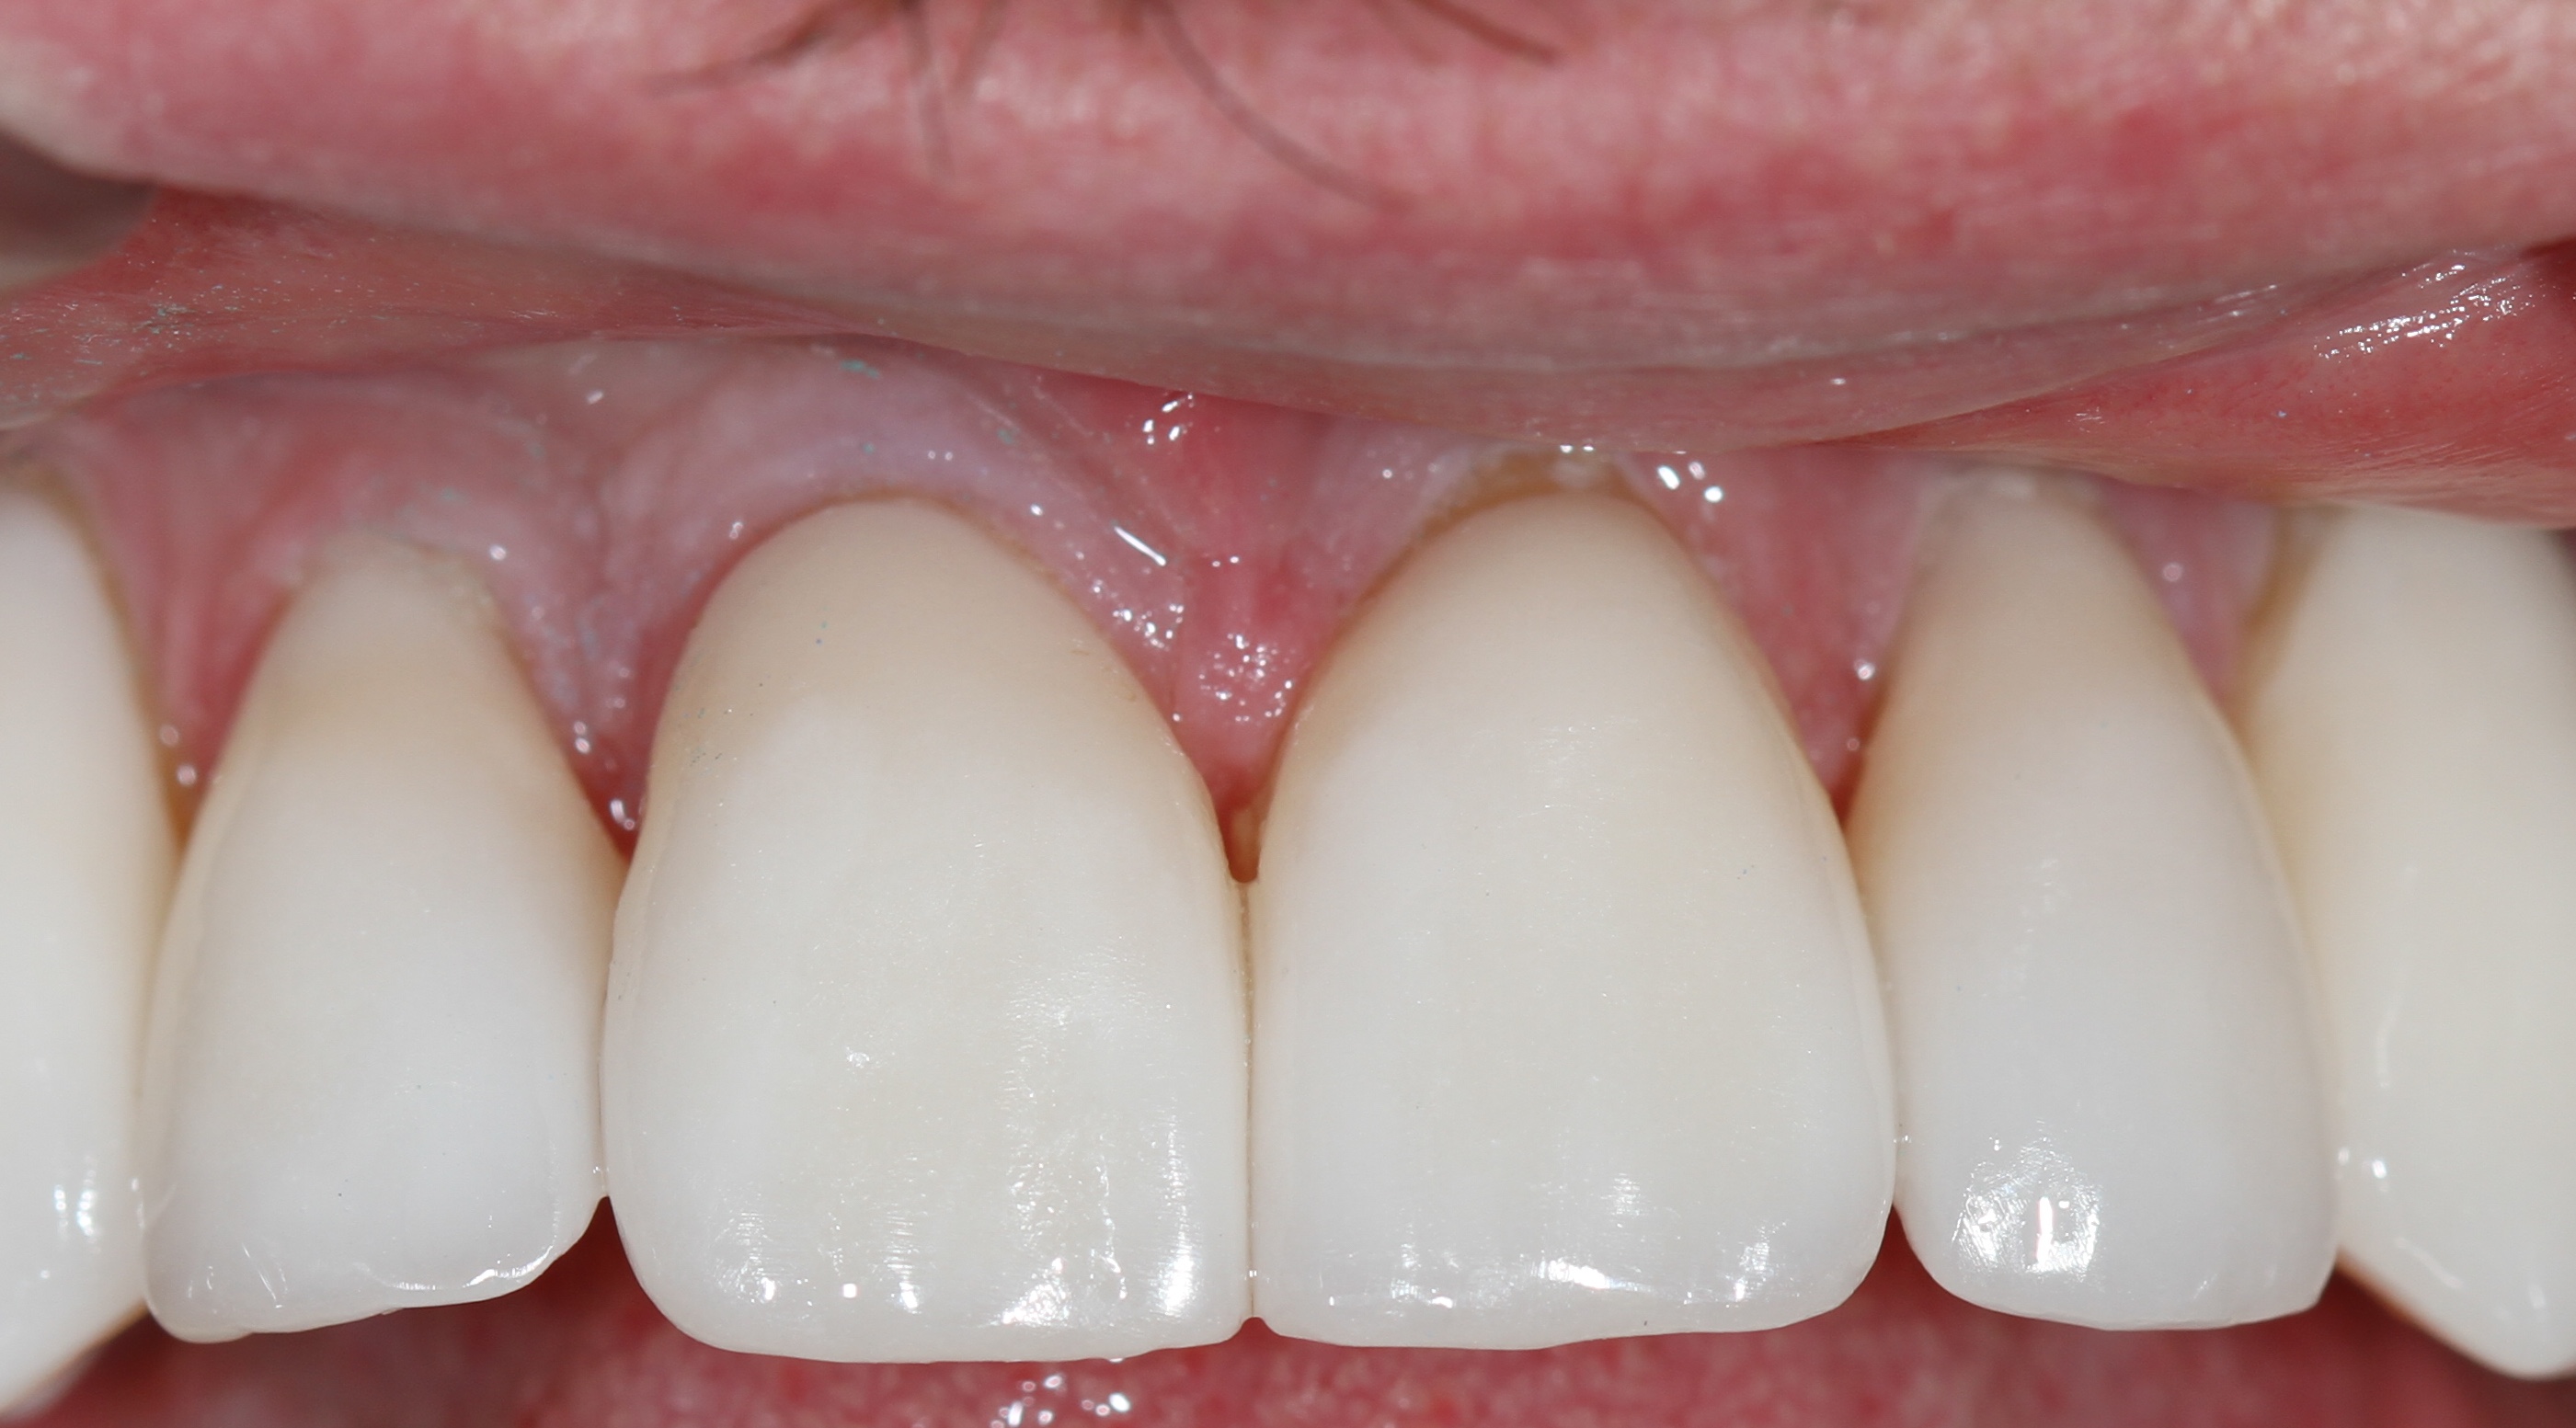

Белые виниры BLEACH

Все чаще стали поступать заказы на виниры цвета BLEACH. Очень красивый результат. Улыбка становится очень красивой.

Это виниры на рефракторе . 12 зуб коронка на оксиде циркония.

Виниры цвета BLEACH

Установлены керамические виниры на верхнюю челюсть по эстетическим требованиям.